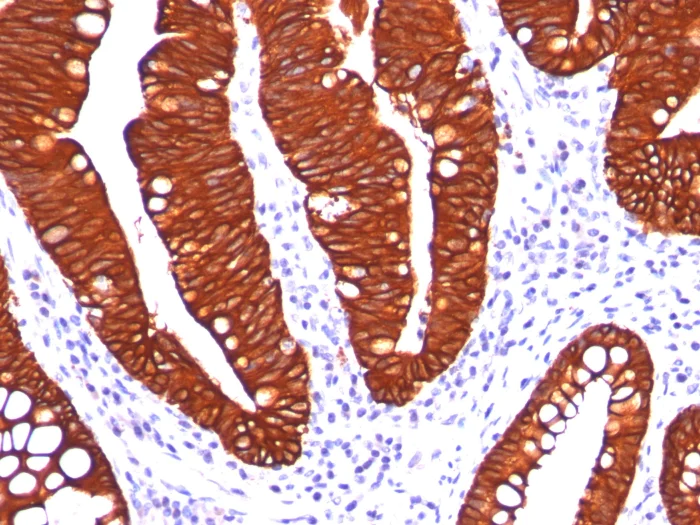

Immunohistochemistry (Formalin/PFA-fixed paraffin-embedded sections) - Anti-Cytokeratin 19 antibody [A53-B] (AB194399)

Immunohistochemistry (Formalin/PFA-fixed paraffin-embedded sections) analysis of human colon carcinoma tissue labelling Cytokeratin 19 with ab194399 at 2 μg/mL for 30 minutes at room temperature. Staining of formalin-fixed tissues requires heating tissue sections in 10mM Tris with 1mM EDTA, pH 9.0, for 45 min at 95°C followed by cooling at room temperature for 20 minutes.